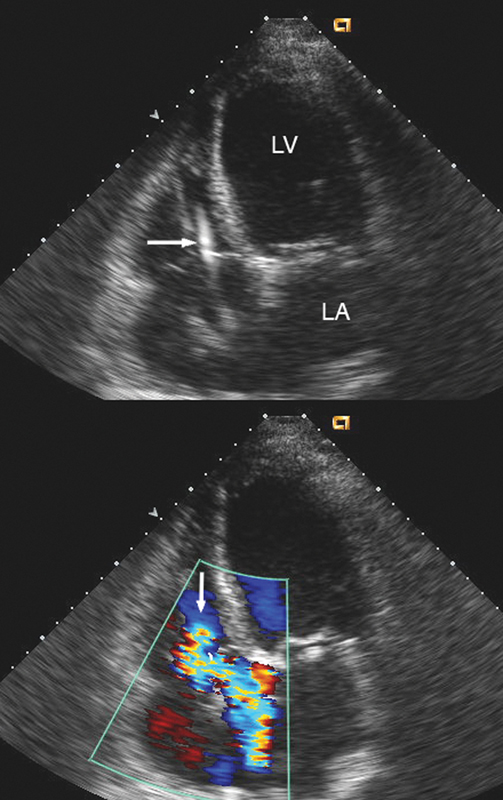

فحوصات تشخيصية لبعض امراض القلب والشرايين التاجية